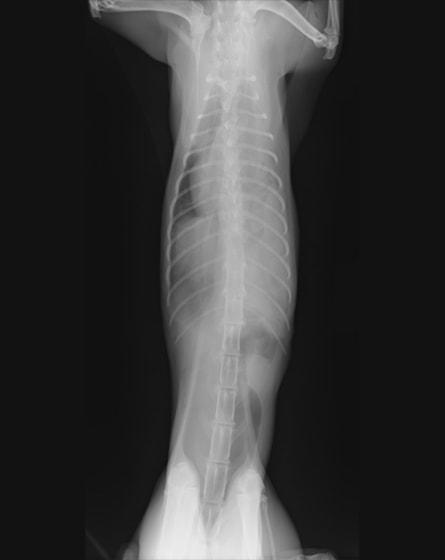

術前レントゲン

腹部臓器が胸腔内に脱出し、腹部と胸部の境界および心臓や肺の陰影が不明瞭になっています。また、胸腔内に消化管のガス陰影が認められます。

術前のレントゲン